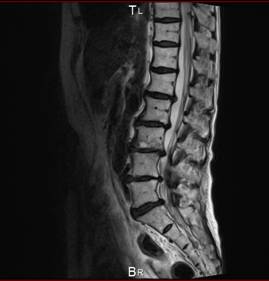

MRI 画像

頚椎、腰椎、のヘルニア、狭窄で痛み、痺れ、マヒ、不眠、が診られ

治療後は症状がとれて痛みや不眠から解放されました。

結果手術をしなくて良くなりました。